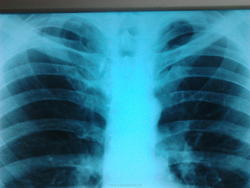

Миргалина! Не надо пугать народ. По обзорной, очагов не наблюдается. Непонятные линейные тени апикально. Отличие от левой по снимку- "100 пудов"- не искл. фиброз.( т.е. на ФЛГ любой увидит, как нью, или б\у-фиброз, а пердидущие где? И если там не было? - ну тода мы все горазды...) Направили на КТ, сами не ожидая успеха, а бок + томку сделать?

КТ:"очажок" оказался каверной.Комментировать.думаю.не стоит. Теперь верите?

Впервые выявленный.Пришел на консультацию.

Миргалина подтвердила убежденность и требовательность главного рентгенолога Радиомеда Катенёва В.Л. о необходимости томографического исследования верхушек легких при подобных изменениях, что и было им неоднократно доказано на клинических примерах с использованием линейной томографии. Теперь в нашем распоряжении сейчас имеется более разрешающий метод, который целесообразно применять для исключения активного туберкулеза при процессах, которые трактуются обычно, как остаточные туберкулезные изменения. Начало положено. Надо накапливать материал.